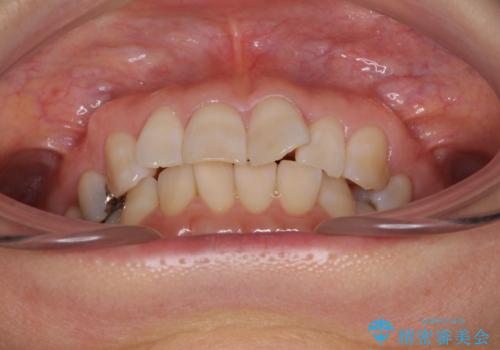

- 前歯のデコボコと上下正中のずれを気にして来院された患者様です。

下顎骨が骨格的にずれがあったため、しっかりと正中を合わせるとなるとワイヤー矯正が必要でしたが、マウスピース矯正を希望されたため、極力正中を合わせることを目標に、インビザラインにて矯正治療を行うこととしました。

インビザラインは、ワイヤー矯正と異なり、患者様がしっかりと使うということが治療成功の絶対必須条件となります。

十分な装着時間が達成できず、治療途中で後戻りを起こすことがあり、インビザラインの有効期限内に終了させることができませんでした。

ワイヤー矯正や別システムのマウスピース矯正を利用することで、何とか終了させることができました。